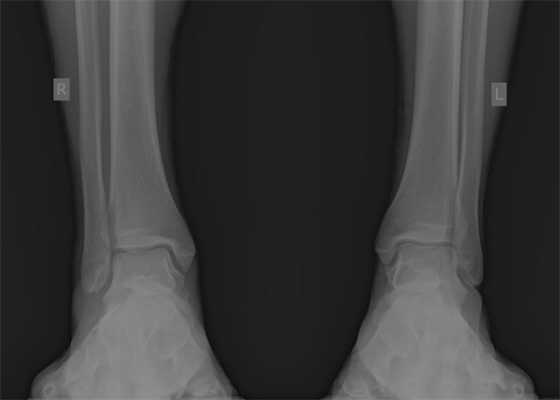

В нашей клинике пациент Ч. Был осмотрен врачом, заподозрено повреждение дистального межберцового синдесмоза, на фоне хронической нестабильнсоти голеностопного сустава. Были выполнены МРТ голеностопного сустава и рентгенография голеностопных суставов стоя с нагрузкой весом тела, а также стресс-рентгенограммы, в вынужденном положении, которые подтвердили диагноз.

Очень важно чтобы при первичном обращении в травмпункт, пациентам с повреждением связочного аппарата голеностопного сустава производились полноценные рентгенограммы, стоя с нагрузкой весом тела, косая проекция с внутренней ротацией голени 15 градусов, а при необходимости, и стресс-рентгенограммы.

При детальном изучении снимков определяется увеличение межберцовой щели до 7,5 мм, уменьшения зоны перекрытия большеберцовой и малоберцовой костей до 5 мм, отсутствие на стороне поражения перекрытия тени таранной кости и малоберцовой кости.

На рентгенограмме костей правого и левого голеностопных суставов в прямой проекциии, снимки стоя - справа определяются признаки повреждения дистального межберцового синдесмоза - степень взаимного перекрытия берцовых костей 5мм (в норме больше 6мм) увеличенное большеберцовое - малоберцовое пространство - 7.5мм (в норме до 6мм).

При выполнении стресс рентгенограмм определяется выраженная латеральная нестабильность голеностопного сустава.